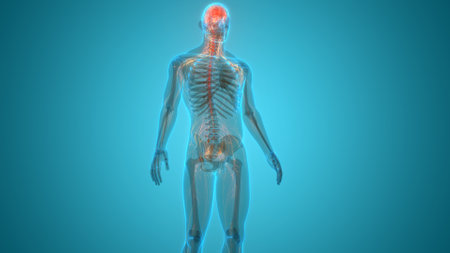

A captivating digital depiction of the human nervous system, highlighting the brain and spinal cord with glowing neural connections, perfect for educational materials.

This artistic visualization depicts the human anatomy, highlighting the brain, spine, and nervous system in vibrant red hues. Aimed at educational and medical audiences, this model enhances comprehension of human physiology.